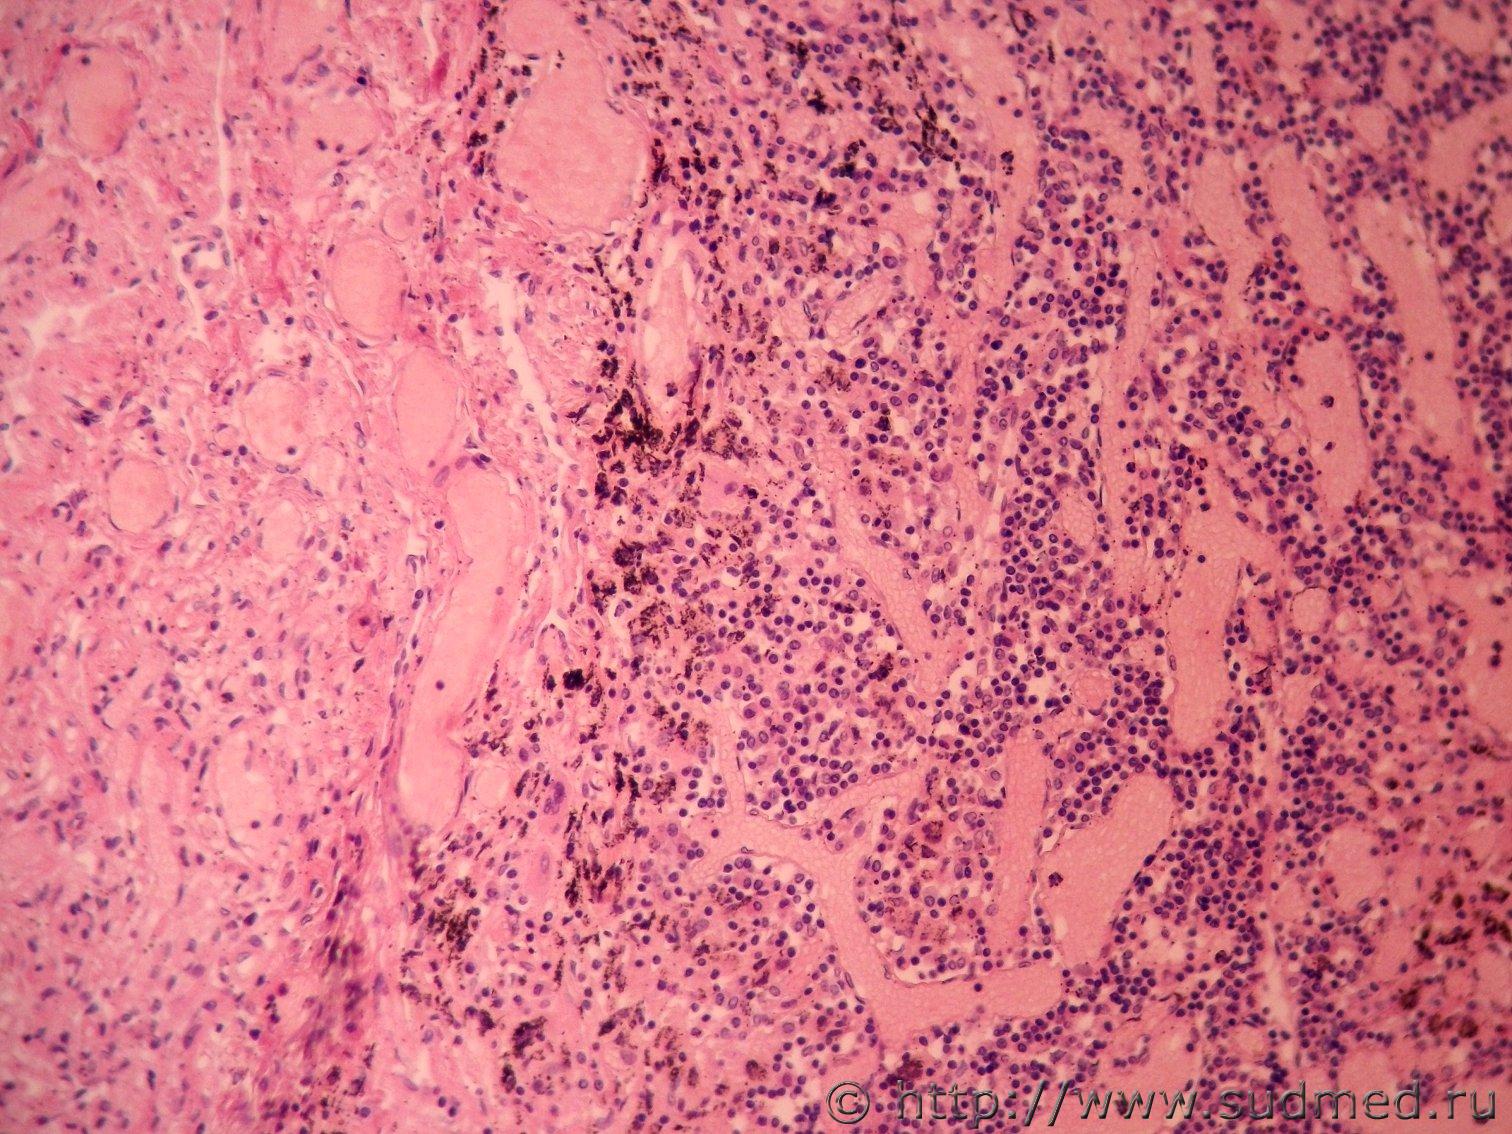

Доброе время дня, уважаемые участники! У коллеги под микроскопом в стеклопрепарате легких умершей женщины (67 лет) выявилось неясное образование. На скорую руку сделал снимки с ув. 40х, 200х и 400х. Прошу помощи и ответа, что бы это могло быть? На опухоль вроде бы не похоже. Что-то из лимфатической системы? Снимки прикрепляю. Заранее благодарю.

Похоже на перибронхиальный лимфоузел.

Спасибо! Да, это может быть ЛУ, вдобавок еще и с антракотическими изменениями.

Еще одну концепцию лимфатических образований в легких выдвигали еще в 70-х годах прошлого века в Киеве доц. Чернышенко и проф. Чернокульский - они описывали т.н. "периваскулярные лимфатические фолликулы" в легких. Половина аудитории их признавала, половина - отвергала.

Посмотрел фото,прочитал по сноске и получается,что на представленных фото "периваскулярный лимфатический фолликул".

Гистологическая картина соответствует Склерозирующей пневмоцитоме(гемангиоме).Попробуйте ИГХ на EMA , TTF1.